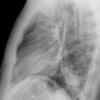

Case 3 RM & UL pneum Lat

Date: 07/04/2004

Views: 6779